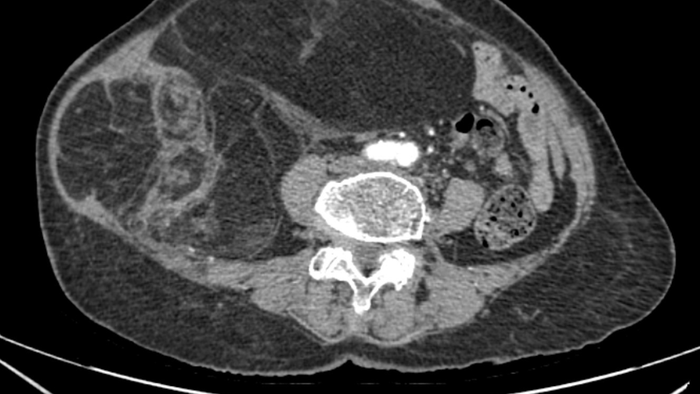

Kết quả chẩn đoán hình ảnh CT ổ bụng có tiêm thuốc cản quang cho thấy khối choán chỗ sau phúc mạc, kích thước khoảng 28 × 15 cm, cấu trúc hỗn hợp tổ chức mỡ – đặc, đè đẩy các tạng trong ổ bụng nhưng chưa xâm lấn tạng lân cận. Bệnh nhân được chẩn đoán sarcoma mỡ sau phúc mạc – một dạng u ác tính mô mềm hiếm gặp.

Hình ảnh phim chụp CT ổ bụng của bệnh nhân